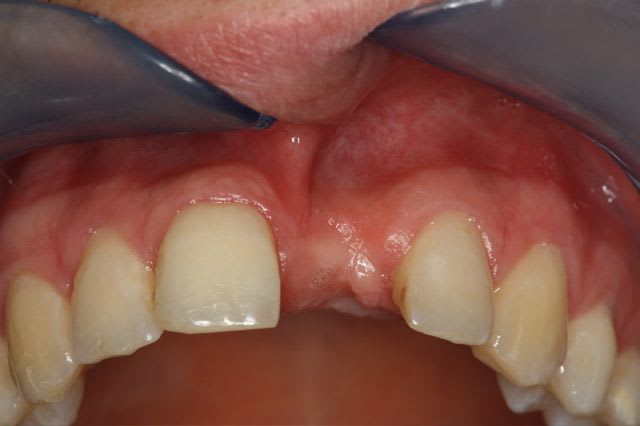

Pour le fun ! car pas bcp de photos en ce moment sur nonol

la dent était absente depuis 8 ans suite à "accident" de la vie (à 5h du mat'...)

dépose des vis et pose de l'implant à 5mois1/2 avec un cj roulé et mise en place de la vis de cica,

et 3 mois 1/2 après empreinte

15j après essayage pilier et biscuit, visite au labo pour "finition en bouche" et 3 h après scellement.